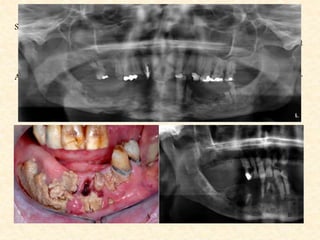

Chronic Suppurative Osteomyelitis

CLINICAL FEATURES

• Fistulae

• “Thickened / Woody” bone

Radiological Features

• In early stage there is widening of marrow spaces giving a

mottled appearance

• Granulation tissue b/w dead & living bone gives irregular lines

& zones of radiolucency resulting in moth -eaten appearance.

• In later stages the devitalized bone appears sclerosed & called

sequestrum.

• Large areas of bone destruction seen as radiolucent areas.